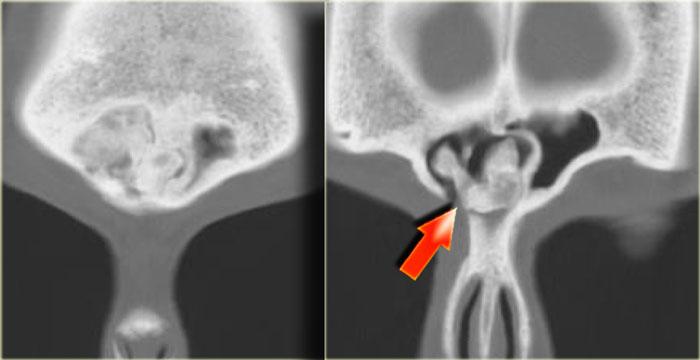

Bên trái là một trường hợp ban đầu được chẩn đoán nhầm là khối u.

Có vật chất tăng tỷ trọng ở xoang sàng sau bên phải, các ngách bướm-sàng hai bên, xoang bướm và có sự xâm lấn vào xương nền sọ (clivus).

Tình trạng tăng tỷ trọng là dấu hiệu tiên lượng tốt, gợi ý một quá trình lành tính.

Đây là ví dụ điển hình của viêm xoang nấm dị ứng.

Thông thường tổn thương này có vị trí ở phía trước hơn.

Bên trái là một ví dụ khác, điển hình hơn, của viêm xoang nấm dị ứng.

Có hình ảnh mờ đục hai bên hốc mũi, thường là dấu hiệu của quá trình viêm hoặc polyp.

Lưu ý hình ảnh phân lớp đồng tâm xen kẽ giữa tăng tỷ trọng và giảm tỷ trọng trong các xoang hàm.

Tình trạng tăng tỷ trọng là do dịch tiết đặc quánh và các thành phần nấm.

Tình trạng giảm tỷ trọng phản ánh các nang, bệnh lý niêm mạc và mô hạt.

Ở vùng xoang sàng, một phần tình trạng tăng tỷ trọng phản ánh viêm màng xương và tân tạo xương dọc theo các vách ngăn.